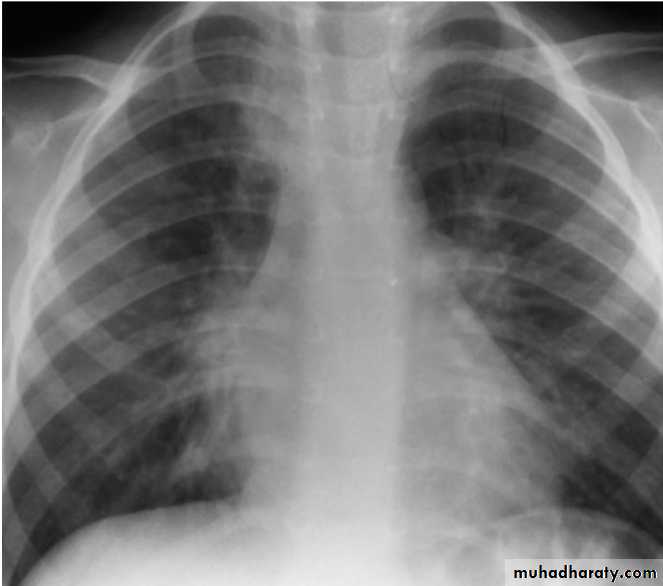

bronchoscopy with bronchoalveolar lavage and brush mucosal biopsy, needle aspiration of the lung, and open lung biopsy are methods of obtaining material for microbiologic diagnosis.Lobar Pneumonia

Bronchopneumonia

CXR:

Frontal & lateral:Bacterial pneumonia characteristically shows lobar consolidation, or a round pneumonia, with pleural effusion in 10% to 30% of cases.

Viral pneumonia characteristically shows diffuse, streaky infiltrates of bronchopneumonia.

Atypical pneumonia, such as with M. pneumoniae and C. pneumoniae, shows increased interstitial markings or bronchopneumonia.